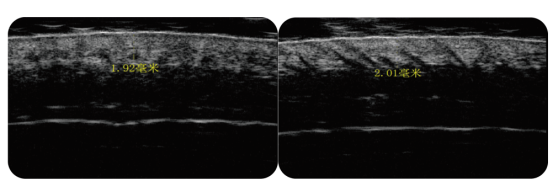

从头皮的构造看,最外面的表皮层帮助防止外界污染和细菌的侵袭,避免敏感、瘙痒、头皮屑等头皮问题。在表皮下方是真皮层,它为表皮提供大量的营养供给和运输代谢物,使皮肤富有弹性和韧性,伸展到真皮层深处的毛囊直接关系到头发和新陈代谢。但如果真皮层受损或缺失,就可能会引起胶原蛋白断裂与流失、弹力纤维萎缩,从而加速皮肤失去弹性、暗沉以及脱发。头皮是面部、颈部皮肤的延续,同时也是毛发赖以生存的土壤。与面颈部皮肤相比,头皮组织更薄、毛囊密度更高、皮脂腺分泌更加旺盛、自由基含量较高,因此更加脆弱、敏感,更易衰老。眼部皮肤厚度约为0.6毫米,脸皮厚度1.533毫米,而头皮厚度大约是1.476毫米,所以头皮是仅次于眼部皮肤的人体第二薄皮肤。头皮的厚度直接关系到头皮弹性与水分的保有度等,并影响着头发生长和孕育的功能。研究文献表明,正常情况下,头皮厚度在30-40岁左右达到顶峰,而后随着年龄的增长慢慢下降变薄。而由于负责头发生长的毛囊位于真皮层,随着真皮层结构的萎缩,毛囊活力下降,自然而然就产生了脱发。头皮皮脂腺密度大约144-192个/平方厘米 ,额头上52-79个/平方厘米,脸颊42-78个/平方厘米。跟面部最容易出油的额头相比,头皮的皮脂腺数量也有它的2倍之多。头皮皮脂腺分泌旺盛,再加上头发的密集结构,极易滞留来自于空气、水等环境中的固体颗粒、液滴和气体污染物等,进一步刺激头部皮肤,造成头皮负担更重、老化更快。不同于一般皮肤细胞28天的新陈代谢周期,头皮细胞代谢周期仅为14-21天,更快的新陈代谢也意味着头皮更加脆弱,也更易衰老。快速的新陈代谢会加速自由基的产生、皮脂腺的分泌,因此也更易引发头皮瘙痒、敏感、炎症、脱发等头皮问题。喜乐注册的头皮长期被紫外线照射,不仅会破坏保护头皮的屏障功能,还会破坏蛋白质和黑色素,对表皮和真皮层结构和功能产生影响,并可能影响到毛囊的重塑。如果紫外线暴露程度严重的话,会引起头皮光老化、头皮暗沉、头皮纤维化,甚至诱发头皮炎症、脱发。

加速血液循环、提升氧气供给,增强头皮血供,促进胶原蛋白及弹性纤维重组再生,改善头皮凹凸不平,增加头皮真皮层厚度,重塑毛囊健康生长微环境,实现头发加密加粗、健发固发。